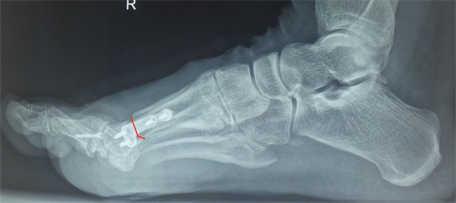

Figure 12. (a) Patient Nr. 3. Hallux valgus, pathologic DMAA; (b) Patient Nr. 3 Elevation of the Ist metatarsal of 3 mm.

Figure 15. Patient Nr. 3. The elevation of the I metatarsal was equalized by plantarization of the head of 3 mm.